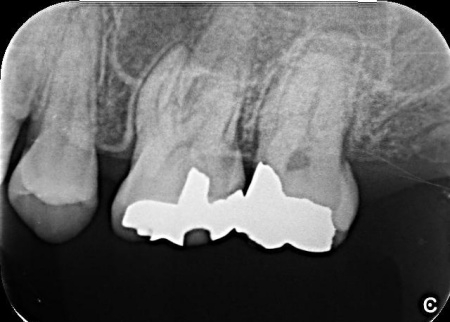

| 行ったご提案・治療内容 | 歯性上顎洞炎を改善するためには、原因となっている歯根内部の細菌をできるだけ除去する必要があります。 また、患者様は「できるだけ歯を残して治したい」と希望されていたことから、精密根管治療を提案しました。 精密根管治療ではマイクロスコープ(歯科用高倍率顕微鏡)を使用し、肉眼では確認が難しい部分を拡大しながら治療を行います。これにより、複雑な根管内部や細かな感染部位まで確認できるため、より精密な処置が可能です。 一方で、根管の形態や感染の程度によっては治療が複数回に及ぶ場合があること、また根管治療を行っても上顎洞炎の改善がみられない場合には、外科的処置や抜歯を検討する必要があることもお伝えしています。 患者様には以上の内容をしっかりとご理解いただいたうえで、治療に同意いただきました。 まずは、左上奥歯に装着されていた既存の詰め物を取り外し、根管内部を確認します。 根管内部の洗浄と消毒が完了したら、根管の内部を密封する処置を行います。 最後にレントゲン撮影を行い、根管がしっかりと封鎖されていることを確認して、治療を終了しています。 |

治療前